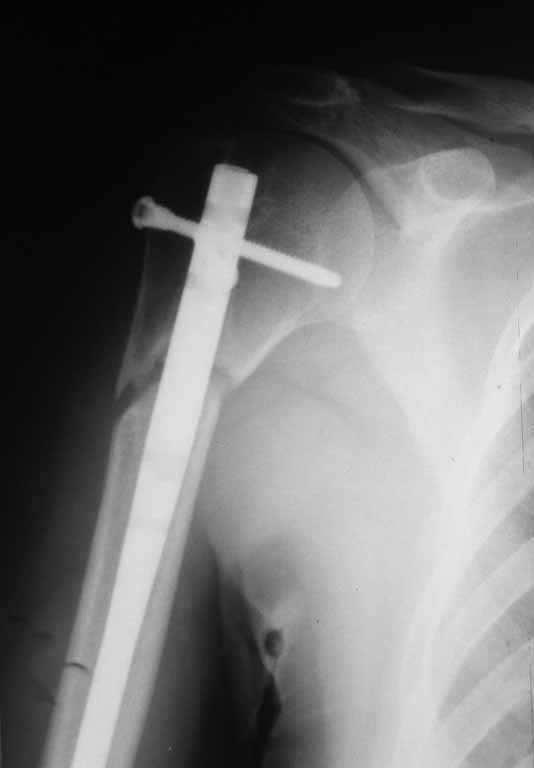

Уважаемые коллеги представляю вашему вниманию пациентку 27 лет с ложным суставом проксимального отдела плечевой кости в условиях БИОС.

Травма 11 мес. назад в результате падения. У нас в клинике на 2-е сутки выполнена закрытая репозиция, БИОС плечевой кости.

После выписки наблюдалась в ЦРБ по м\ж. Спустя такое большое количество времени направлена к нам для контрольного осмотра с жалобами на умеренный болевой синдром. На контрольных рентгенограммах имеются признаки ложного сустава проксимального отдела плечевой кости. Пациентка запланирована на госпитализацию.Прошу совета в тактике оперативного лечения.

На этом снимке результат дистракции, а происхождение дистракции без полного снимка плеча трудно увидеть. (насчет стандартных снимков писали неоднократно, но по-прежнему показывают короткие снимки без захвата даже всей длины имплантата) Дистракция обычно происходит, когда длинный гвоздь упирается в узкой части в дистальном отделе, или при отсутствии дистальной блокировки, когда отломок скользит по гвоздю.